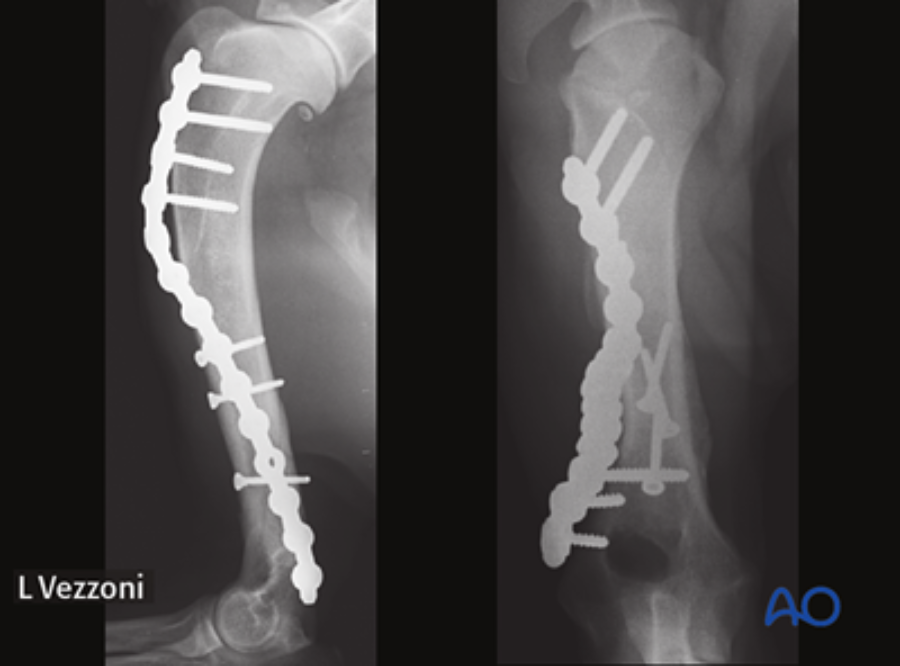

The module on this anatomical area was authored by Martin Unger (Germany). Matthew J Allen (UK) and Aldo Vezzoni (Italy) acted as editors.

This module follows the AO VET classification for long bones. It offers an in-depth description of both lateral and medial approaches, along with a detailed exploration of a minimally invasive approach for the dog humeral shaft.

It encompasses both nonsurgical and surgical management techniques, providing detailed insights into the utilization of plates, intramedullary pins, and interlocking nails for fixation. Additionally, it offers supplementary reading materials that highlight the anatomical distinctions between dogs and cats, as well as the most prevalent complications that arise during humeral shaft fracture management.

Matthew Allen: For me, the most interesting part of the module relates to the use of locking plates, especially in the context of minimally invasive surgical approaches. This method’s advantages include a combination of periosteal preservation and superior stability, which is achievable by locking the screw head directly into the plate. Where this approach is indicated, it is an excellent option for humeral shaft and humeral condylar fractures.